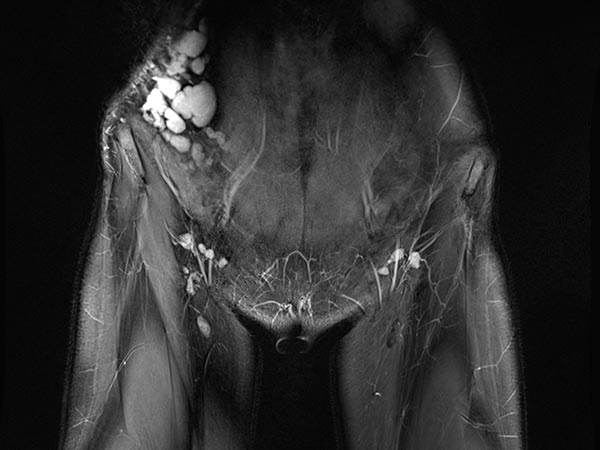

Coronal, T2-weighted, fat-suppressed MRI of the lower abdomen at the level of the groin. Normal inguinal lymph nodes. The lymphatic malformation of the abdominal wall presents as large, dysplastic, balloon-like, septated cysts that are grossly hyperintense (white).